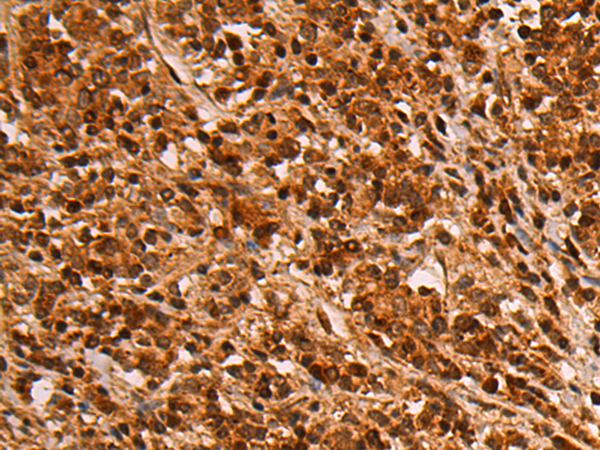

分类: 科研抗体货号: P01378别名: SLIM2应用: WB,IHC反应种属: Human, Mouse

分类: 科研抗体货号: P01441别名: RNMX; HNRPG; HNRNPG; RBMXP1; RBMXRT; hnRNP-G应用: WB,IHC反应种属: Human, Mouse, Rat

分类: 科研抗体货号: P01373别名: FHFR; FGFR5应用: WB,IHC反应种属: Human, Mouse, Rat

分类: 科研抗体货号: P01433别名: HL; HTGL; LIPH; HDLCQ12应用: WB,IHC反应种属: Human, Mouse

分类: 科研抗体货号: P01458别名: CBAS1; PFIC4; SDR11E3应用: IHC反应种属: Human, Mouse, Rat

分类: 科研抗体货号: P01432别名: HCCR; HCCR1; HCCR2; HCCR-1; HCCR-2; HCRR-2; SLC55A3; 1110019O13Rik应用: WB,IHC反应种属: Human, Mouse

分类: 科研抗体货号: P01454别名: HSE; RODH; SDR9C6应用: WB,IHC反应种属: Human, Mouse

分类: 科研抗体货号: P01426别名: CSA; MOT; MOT2; GRP75; PBP74; GRP-75; HSPA9B; MTHSP75; HEL-S-124m应用: WB,IHC反应种属: Human, Mouse, Rat

分类: 科研抗体货号: P01425别名: GPRK5; FP2025应用: IHC反应种属: Human, Mouse, Rat